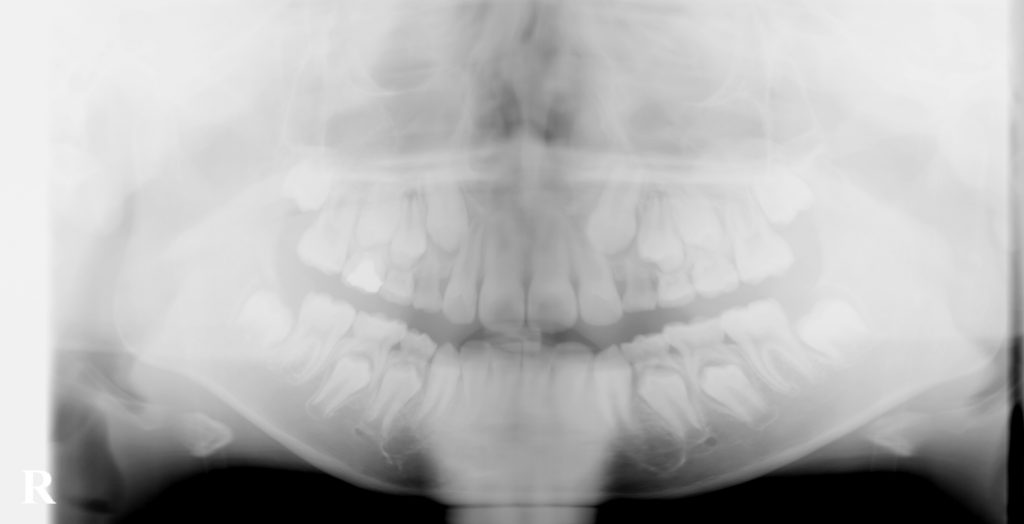

こむら小児歯科・矯正歯科で経過観察してきたケースです。

上の犬歯の位置が悪かったのですが、最終的には問題なく生えてきました。

どんなケースでも矯正治療が必要というわけではなく、正しい診断の元に経過観察することも大切です。

埋まっている上の犬歯を引っ張らなくても このようにきれいに生えてくる事もあります。